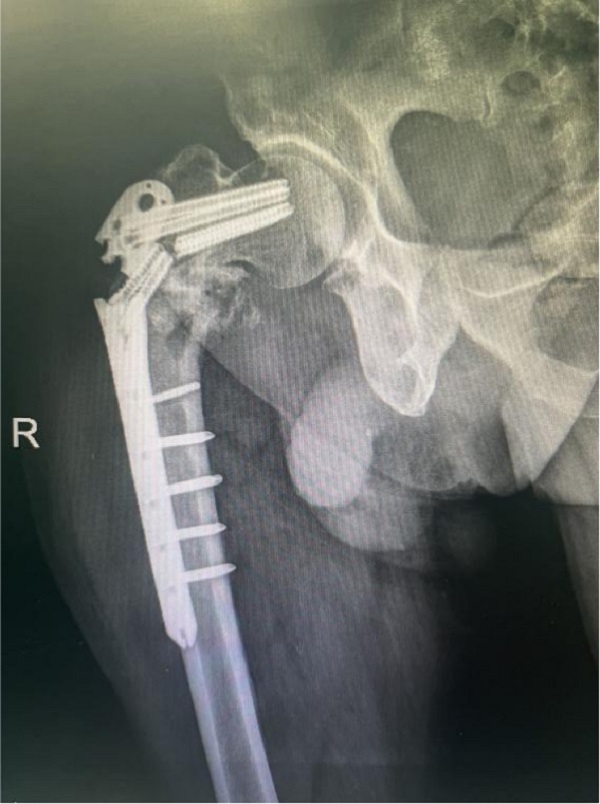

退休李师傅今年79岁,4个月前因右侧股骨近端病理性骨折在外院行瘤体切除,钢板内固定手术。近期下地活动时轻微扭伤后感右大腿根部疼痛伴活动受限,来陕健医二一五医院拍片提示:右股骨近端骨折术后再骨折伴内固定断裂。老年患者的股骨近端骨折若不积极正规治疗,可能因长期卧床引起肺部感染、泌尿系感染、深静脉血栓、褥疮等并发症,被称为“人生的最后一次骨折”。

术前X片: